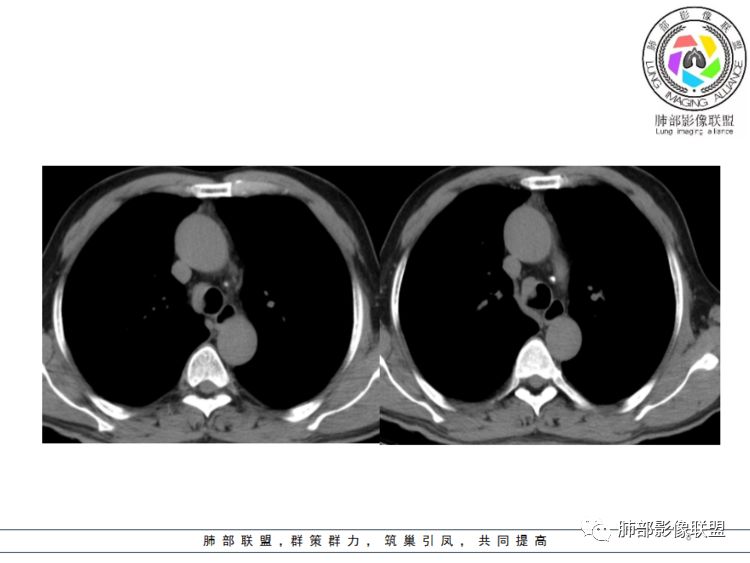

傅昌瑜:55岁男性,右侧气管下段偏前侧后壁见软组织密度结节(无增强,但目测其密度与肌肉差不多,且镜下见为肿物),考虑为气管肿瘤;定性:结节基底部大于其最大横径(宽基底),结节与气管内壁的夹角呈钝角,无蒂,结节周围气管壁增厚僵硬,向纵隔侵犯,故考虑为恶性。气管内恶性肿瘤常见有鳞状细胞癌(最常见)、腺样囊性癌、粘液表皮样癌、类癌。年轻女性类癌相对多见,腺样囊性癌、粘液表皮样癌位置可能与腺体分布有关,多位于气管后方或侧后方。具体到这个病人考虑:气管鳞状细胞癌

Coke with ice:体检发现,软组织密度,边缘规整,病灶主体沿气管外缘走行,大部位于管腔外,局部向腔内突入,邻近气管软骨未见明显破坏,考虑良性病变

生来征服-浪子:患者中年,无任何临床症状,气管右侧壁软组织密度影,宽基底位于气管壁,向腔内腔外生长,形态规则,首先考虑良性或者低度恶性肿瘤。无任何阻塞性表现,不考虑鳞癌

病灶跨气管壁内外,主体在外;边界清,密度均匀

明显看到气管壁软骨受压内移

局部是撑开的,就是说软骨不是破坏

表面隆起,有小斑点

无症状;倾向于良性,平滑肌瘤?神经源性肿瘤?不除外其他

南边分析:针对本例,病灶跨气管壁内外生长,常规跨内外的有:恶性肿瘤为主,其次就是神经源性、平滑肌瘤;常规的思维:跨内外就要看结构的变化气管的优势在于软骨相对密度高,而且成C型

我们如何分析这个病例?冠状位:软骨密度稍高;病灶区软骨部分区域不连续,外围连续,提示病灶推移为主,不是破坏为主;如果破坏,应该这些软骨显示不清,移位不明显

病灶从软骨见推移开,跨内外,因此定在良性。恶性是侵犯,破坏为主,如果破坏,应该这些软骨显示不清,移位不明显,不是推移为主这例病变定在良性,我们就要考虑:1、软骨之间的平滑肌来源;2、神经源性

病例小结      气管神经鞘瘤属于罕见的气管良性肿瘤,一般气管良性肿瘤或腔内或腔外生长的结节样改变,恶性肿瘤呈腔内外生长,但本例肿块向腔外生长,呈“冰山样改变”,即肿瘤的腔内部分较小而腔外部分较大,无周围组织侵犯。因此肿瘤腔内外生成不能作为鉴别气管良恶性肿块的绝对依据。        因此冠(矢)状位多平面观察、软骨是否破坏、气管壁有无增厚等细节观察,对于鉴别气管肿块良恶性有重要的参考性。

2.影像学病灶占据腔内外,但病灶边缘十分清楚。这点倾向良性。

3.男性气管内肿瘤以发生于粘膜上皮的鳞癌最为常见,本例没有软骨破坏,病灶没有沿气管粘膜表面生长蔓延不支持。